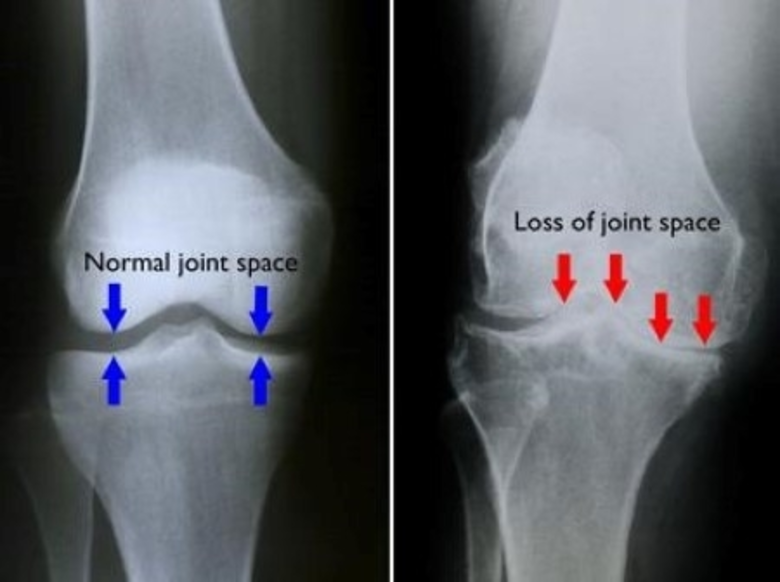

อาการเข่าเสื่อม เกิดจากอะไร โดยปกติแล้ว ก... โรคเข่าเสื่อม รักษาได้ ไม่ต้องผ่าตัด — อาการเข่าเสื่อม เกิดจากอะไร โดยปกติแล้ว กระดูกข้อของเราแต่ละชิ้นจะมีกระดูกอ่อนเชื่อมติดกันอยู่ในบริ...

Osteoarthritis is the most common form of arthritis. It causes pain, swelling and reduced motion in your joints. It can occur in any joint, but usually affects your hands, knee, hips or spine. Thailand Osteoarthritis...